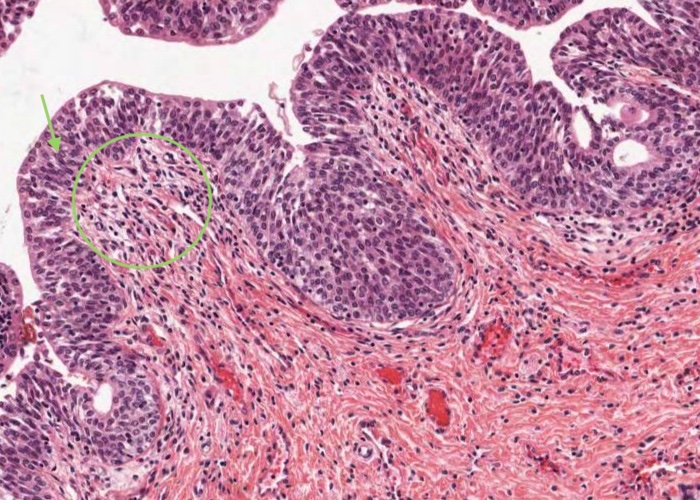

The mucosa has longitudinal folds which you may now appreciate better if you relook at the low magnification image in the previous item. The epithelium of the urethra will vary according to the region from which a section is taken. In this image, taken near the bladder, it is urinary/transitional epithelium (urothelium), at the external opening it is stratified squamous epithelium, and between those two ends the epithelium is pseudostratified or stratified columnar.

Small outpocketings of mucus-secreting cells form clusters in the epithelium and extend into the lamina propria as simple paraurethral glands. Those located within the epithelial layer are examples of intra-epithelial glands.